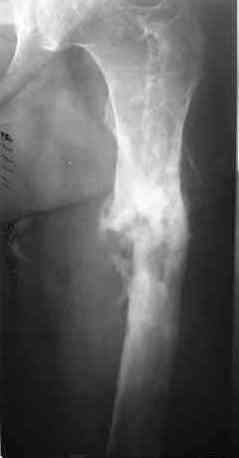

Через 4,5 лет после травмы выявлены рентгенологические признаки консолидации перелома, признаки хронического остеомиелита купировались. Аппарат был демонтирован. Пациент продолжил ходьбу с дозированной нагрузкой на конечность при помощи костылей. Через 2 месяца начал ходить при помощи трости. Однако, еще через 2 месяца отметил появление свищей на бедре с гнойным отделяемым и укорочение длины конечности. При осмотре в январе 2007 г.: пациент ходит при помощи костылей без опоры на левую нижнюю конечность, на бедре имеются множественные рубцы, на наружной поверхности сегмента в верхней и нижней третях имеются два свищевых хода со скудным серозно-гнойным отделяемым; отечности тканей конечности нет, пальпация безболезненная, отмечается укорочение длины конечности на 5 см, патологическая подвижность не определяется, имеется стойкая разгибательная контрактура коленного сустава (разгибание - 180 гр, сгибание - 170 гр), признаков нарушения кровоснабжения и иннервации тканей конечности нет. Температура тела нормальная. В общих анализах крови и мочи отклонений от нормы нет. [image 06,07, 08 (стрелками отмечены свищевые раны, 09, 10]Дорогие коллеги, я уверен, что у многих из вас после знакомства с данным клиническим наблюдением появится множество вопросов, касающихся уже проведенного лечения (особенно, сроков и способов). Сразу оговорюсь - я не смогу правильно ответить на многие вопросы (особенно касающиеся предшествующего периода лечения). Прошу вас, конечно по возможности, сосредоточить внимание не на разборе допущенных ошибок (проведенного лечения), а помочь добрым советом относительно тактики наших дальнейших действий. Наверное, кто-то располагает бесценным опытом лечения подобной патологии.